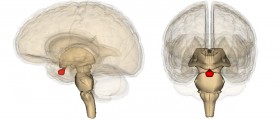

Hormone Replacement After Pituitary Gland Surgery

Medical Answer